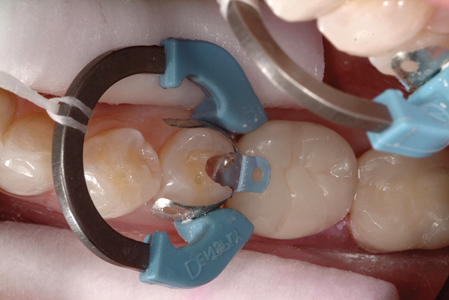

Incorporating Glass Ionomers into Everyday Dental Practice

Snyder Case 3 Class II-3 alternate text for this image

Introduction General dentists in private practice place numerous direct tooth colored resin restorations because of patient demand for more aesthetically pleasing restorations. In other instances, they utilize tooth colored adhesive dentistry because of its benefits of minimally invasive preparation design and adhesive retention to preserve tooth structure. The placement of these indirect and direct tooth … Read more